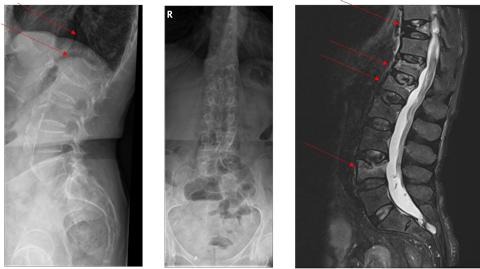

Röntgen LWS + MRT LWS:

Bone images

Bei der Patientin liegt einerseits eine hochgradig reduzierte Knochenmineraldichte vor im Sinne einer sekundären manifesten Osteoporose mit multiplen atraumatischen Wirbelkörperfrakturen und andererseits zusätzlich eine Osteomalazie. Die Ursache der Osteomalazie liegt in der Malabsorption, trotz hochdosierter Vitamin D Substitution liegt ein Mangel vor. Zudem wird zu wenig Calcium über den Gastrointestinaltrakt aufgenommen. Konsekutiv erhöht sich das Parathormon um Calcium aus dem Knochen zu mobilisieren. Davon zu unterscheiden ist ein primärer Hyperparathyreoidismus, welcher zu einer Erhöhung des Serum-Calciumspiegels auf Basis einer autonomen Parathormonproduktion führt.